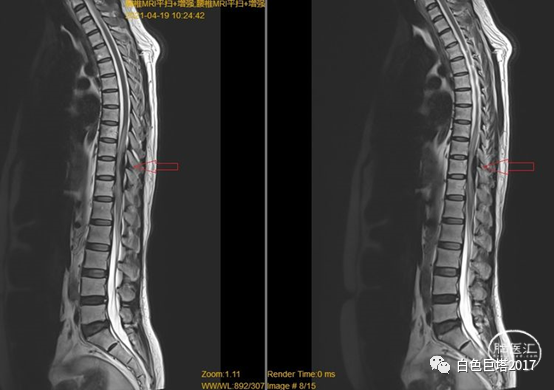

考虑患者体格检查结果与既往病史不符合,患者语言功能障碍,不能很好配合检查。请我科会诊,急诊完善胸腰椎磁共振平扫+增强。

图示:T1

图示:T2,红色箭头所示T10-T12水平椎管内硬脊膜外低信号。

图示:T2压脂像,T8椎体血管瘤。

T2水平面可见相应节段脊髓明显受压。